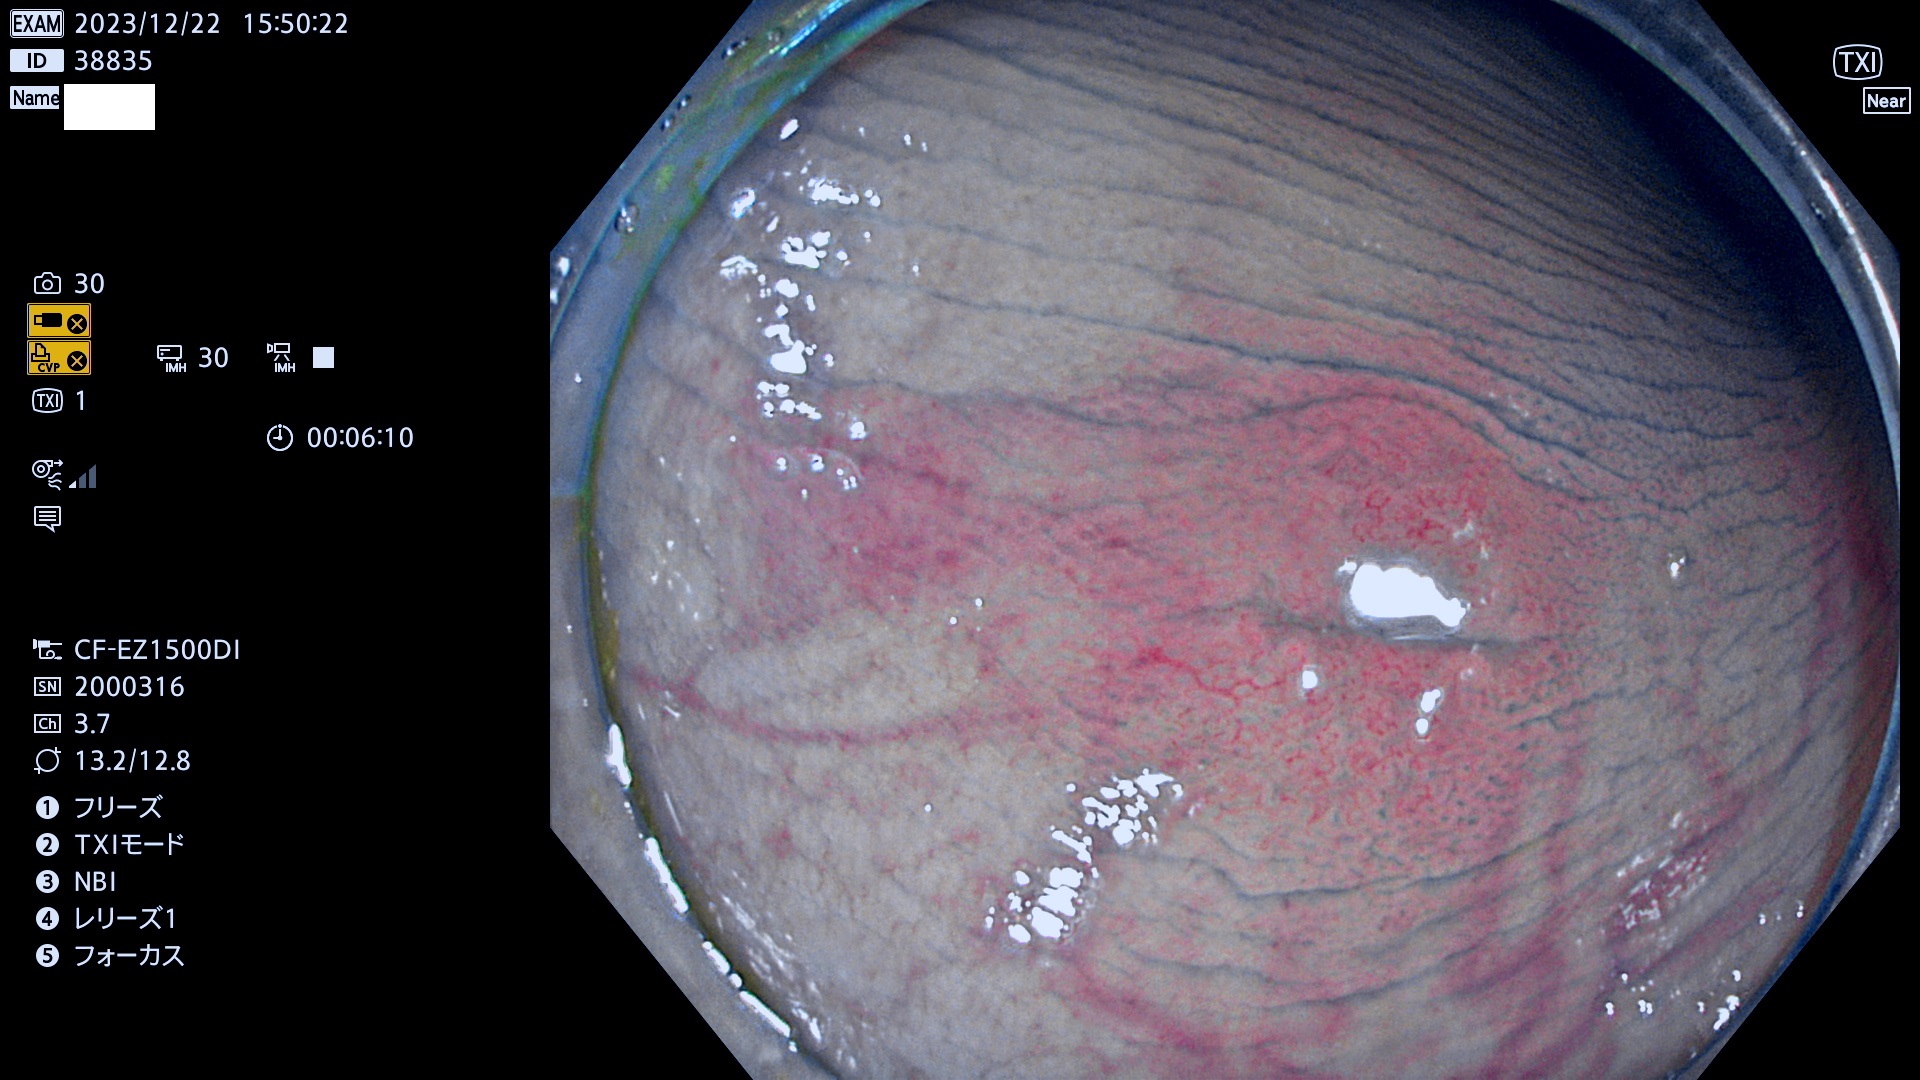

表面型腺腫(Flat Adenoma)の中で、完全に平坦な物をUb、陥凹している物をUcと呼びます。平坦隆起型(Ua)よりも、発見が難しく危険な病変です。

当院で見つかった、炎症(ビラン)と極めて紛らわしい腺腫の例